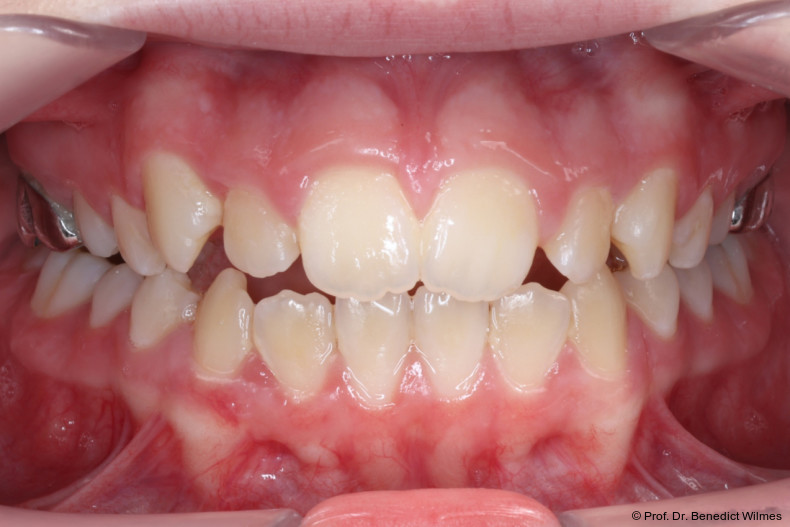

Eine 13-jährige Patientin stellte sich mit beidseitigem Kreuzbiss, einem anterioren offenen Biss und einer Angle Klasse II vor. Das viszerale Schluckmuster wurde mittels logopädischer Maßnahmen umgestellt, der offene Biss persistierte jedoch (Abb. 3a–l).

Als alternative Therapie wurde die chirurgische Korrektur des offenen Bisses nach Abschluss des Wachstums vorgeschlagen. Eltern und Patientin entschieden sich allerdings für die non­chirurgische und weniger invasive Molarenintrusion.